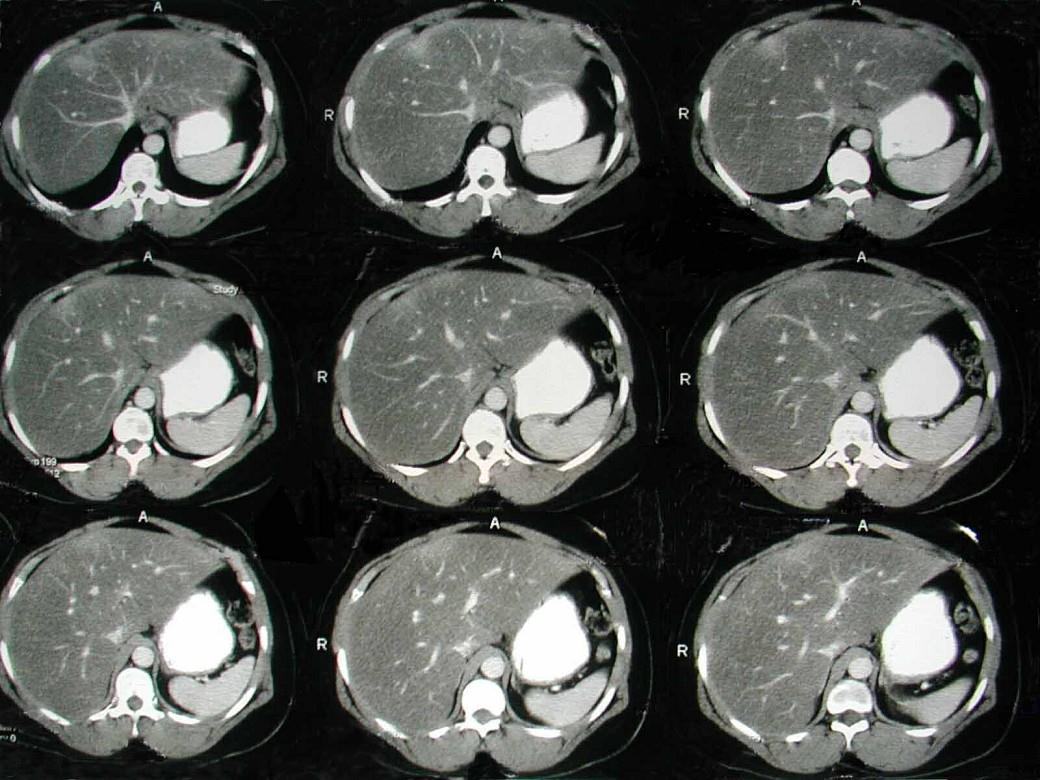

下列图像最可能的诊断是 ( )A.脂肪肝B.肝囊肿C.肝血管瘤D.原发性肝癌E.肝炎肝硬化

问题 下列图像最可能的诊断是 ( )

选项 A.脂肪肝 B.肝囊肿 C.肝血管瘤 D.原发性肝癌 E.肝炎肝硬化

答案 A